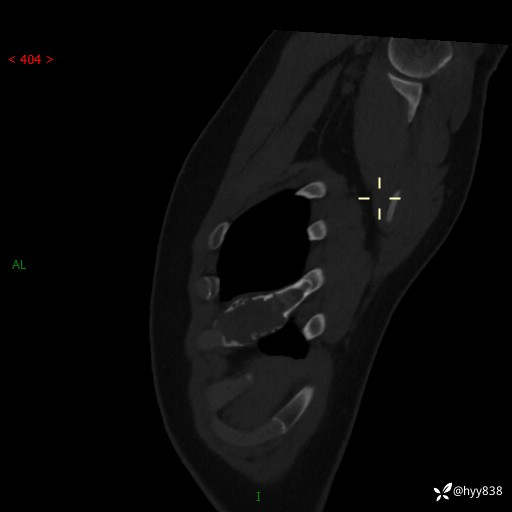

年龄:24岁

主诉:右侧胸部疼痛4天余。

现病史:患者约4天前突发右侧胸部疼痛,无瘙痒,无头痛、头晕,无心慌、胸闷、呼吸困难、咳嗽、咳痰、咯血,无腹痛、腹胀等不适,未作进一步诊治。于2024年5月外院行胸部CT平扫示右侧肋骨骨质改变。现为求进一步治疗,遂于我院就诊。门诊以“胸壁肿物”收入我科。 患者自起病以来,精神可,睡眠可,饮食可,大小便正常,体重无明显改变。

胸部CT平扫